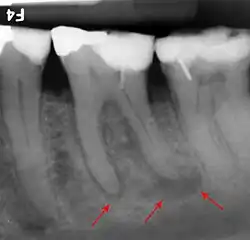

The inferior alveolar nerve (IAN), a branch of the trigeminal nerve (cranial nerve V), is a nerve that runs through the mandible (lower jaw) and supplies sensation to all the lower teeth, the lip and the chin. The lower teeth, and in particular the lower wisdom teeth, can therefore be in close proximity to this nerve. Damage to the inferior alveolar nerve is a risk of lower wisdom tooth removal (and other surgical procedures in the mandible).[20] This means there is a risk of temporary or permanent numbness or altered sensation to the lip +/− chin on the side the surgery is taking place. Therefore, in order to assess this risk and inform the patient, the position of the inferior alveolar nerve in relation to a lower wisdom tooth needs to be assessed radiographically prior to extraction.[20]

The proximity of the root to the canal can be assessed radiographically and there are several factors which can indicate high risk of nerve damage:[21]

- Darkening of the tooth root where it crosses the canal[21]

- Deviation of the canal[21]

- Narrowing of the roots[21]

- Loss of the lamina dura of the canal[21]

- Juxta apical area: a radiolucency associated with the root of the tooth which is not caused by periapical infection[21]